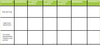

Study and understand the chart comparing the somatosenory pathways.

Try filling in the blanks for practice

Study and understand the chart comparing the somatosenory pathways